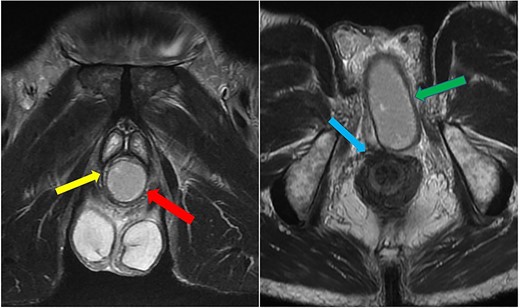

Imaging was suggestive of an infected Cowper’s syringocele. As the patient was clinically stable, a trial of antibiotic therapy was suggested. Repeat MRI a week later showed that the collection had extended into the corpus spongiosum, which now appeared expanded with the fluid density signal (Fig. 1). On a review, the urethral catheter was thought to be impairing potential drainage of the collection. It was removed, and a suprapubic catheter was inserted. Ultrasound guided aspiration failed to drain a significant amount of pus, which also grew S. anginosus. There was also radiological suspicion of a colovesical fistula. The patient was reviewed by the colorectal surgeons, who felt that as there were no other symptoms relating to the fistula, and the patient was physiologically frail, and defunctioning of the bowel would be inappropriate. Likewise, the patient was deemed too frail for any surgical management of the collection. He was discharged after a total of 6 weeks’ antibiotics. Repeat MRI 4 months later (Fig. 2) showed a smaller but persistent collection.

Case 1: T2-weighted axial image 4 months later, showing slight reduction in the size of the collection (arrow).

In view of his significant comorbidities and the absence of any clinical signs or symptoms, he is being managed conservatively with a long-term suprapubic catheter.